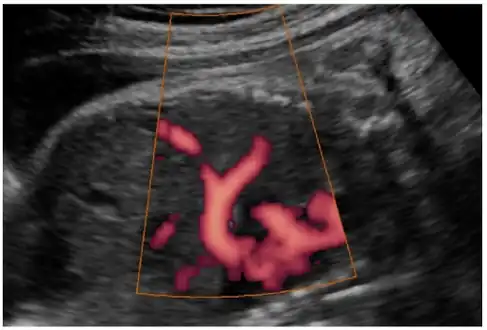

In most cases, postnatal diagnosis is done and up to 2011, only four cases are reported via prenatal diagnosis.[3] Congenital diaphragmatic hernia and intrauterine growth retardation (these two signs put the patients at the risk of afflicting with ring chromosome 15) by fetal ultrasound (Obstetric ultrasonography) at the time period of 16–24 weeks, further investigation and diagnostics (such as karyotyping) must be performed to test the possibility of ring chromosome 15.

Ultrasound finding in a fetus showing liver herniation into the thorax -

Congenital diaphragmatic hernia